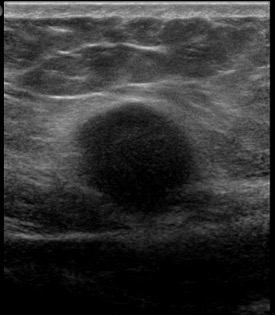

Results of an abdominal examination revealed a deep-seated, firm to hard mass with indistinct margins that appeared to be arising from or firmly attached to the anterior abdominal wall muscle. Results of an ultrasonography scan suggested a probable cystic mass in the subcutaneous tissues of uncertain etiology (Figures 1 and 2).

Figure 1. An ultrasonography scan of the abdomen revealed a mass to the right of the midline in transverse orientation that was 1.96 cm deep.